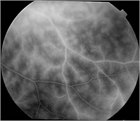

1. ベーチェット病は、皮膚粘膜病変を特徴とする、原因不明の全身性炎症性疾患で指定難病である。